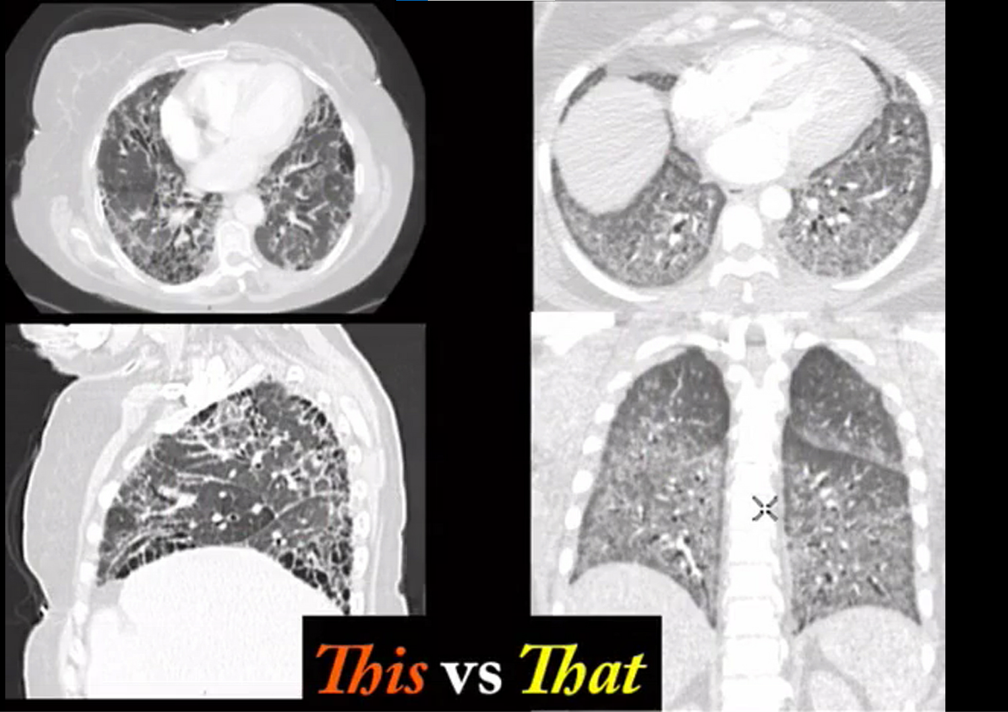

Pulmonary alveolar proteinosis

ground glass plus crazy paving

treatment = bronchoalveolar lavage

middle aged woman with chronic mild SOB. No smoking history